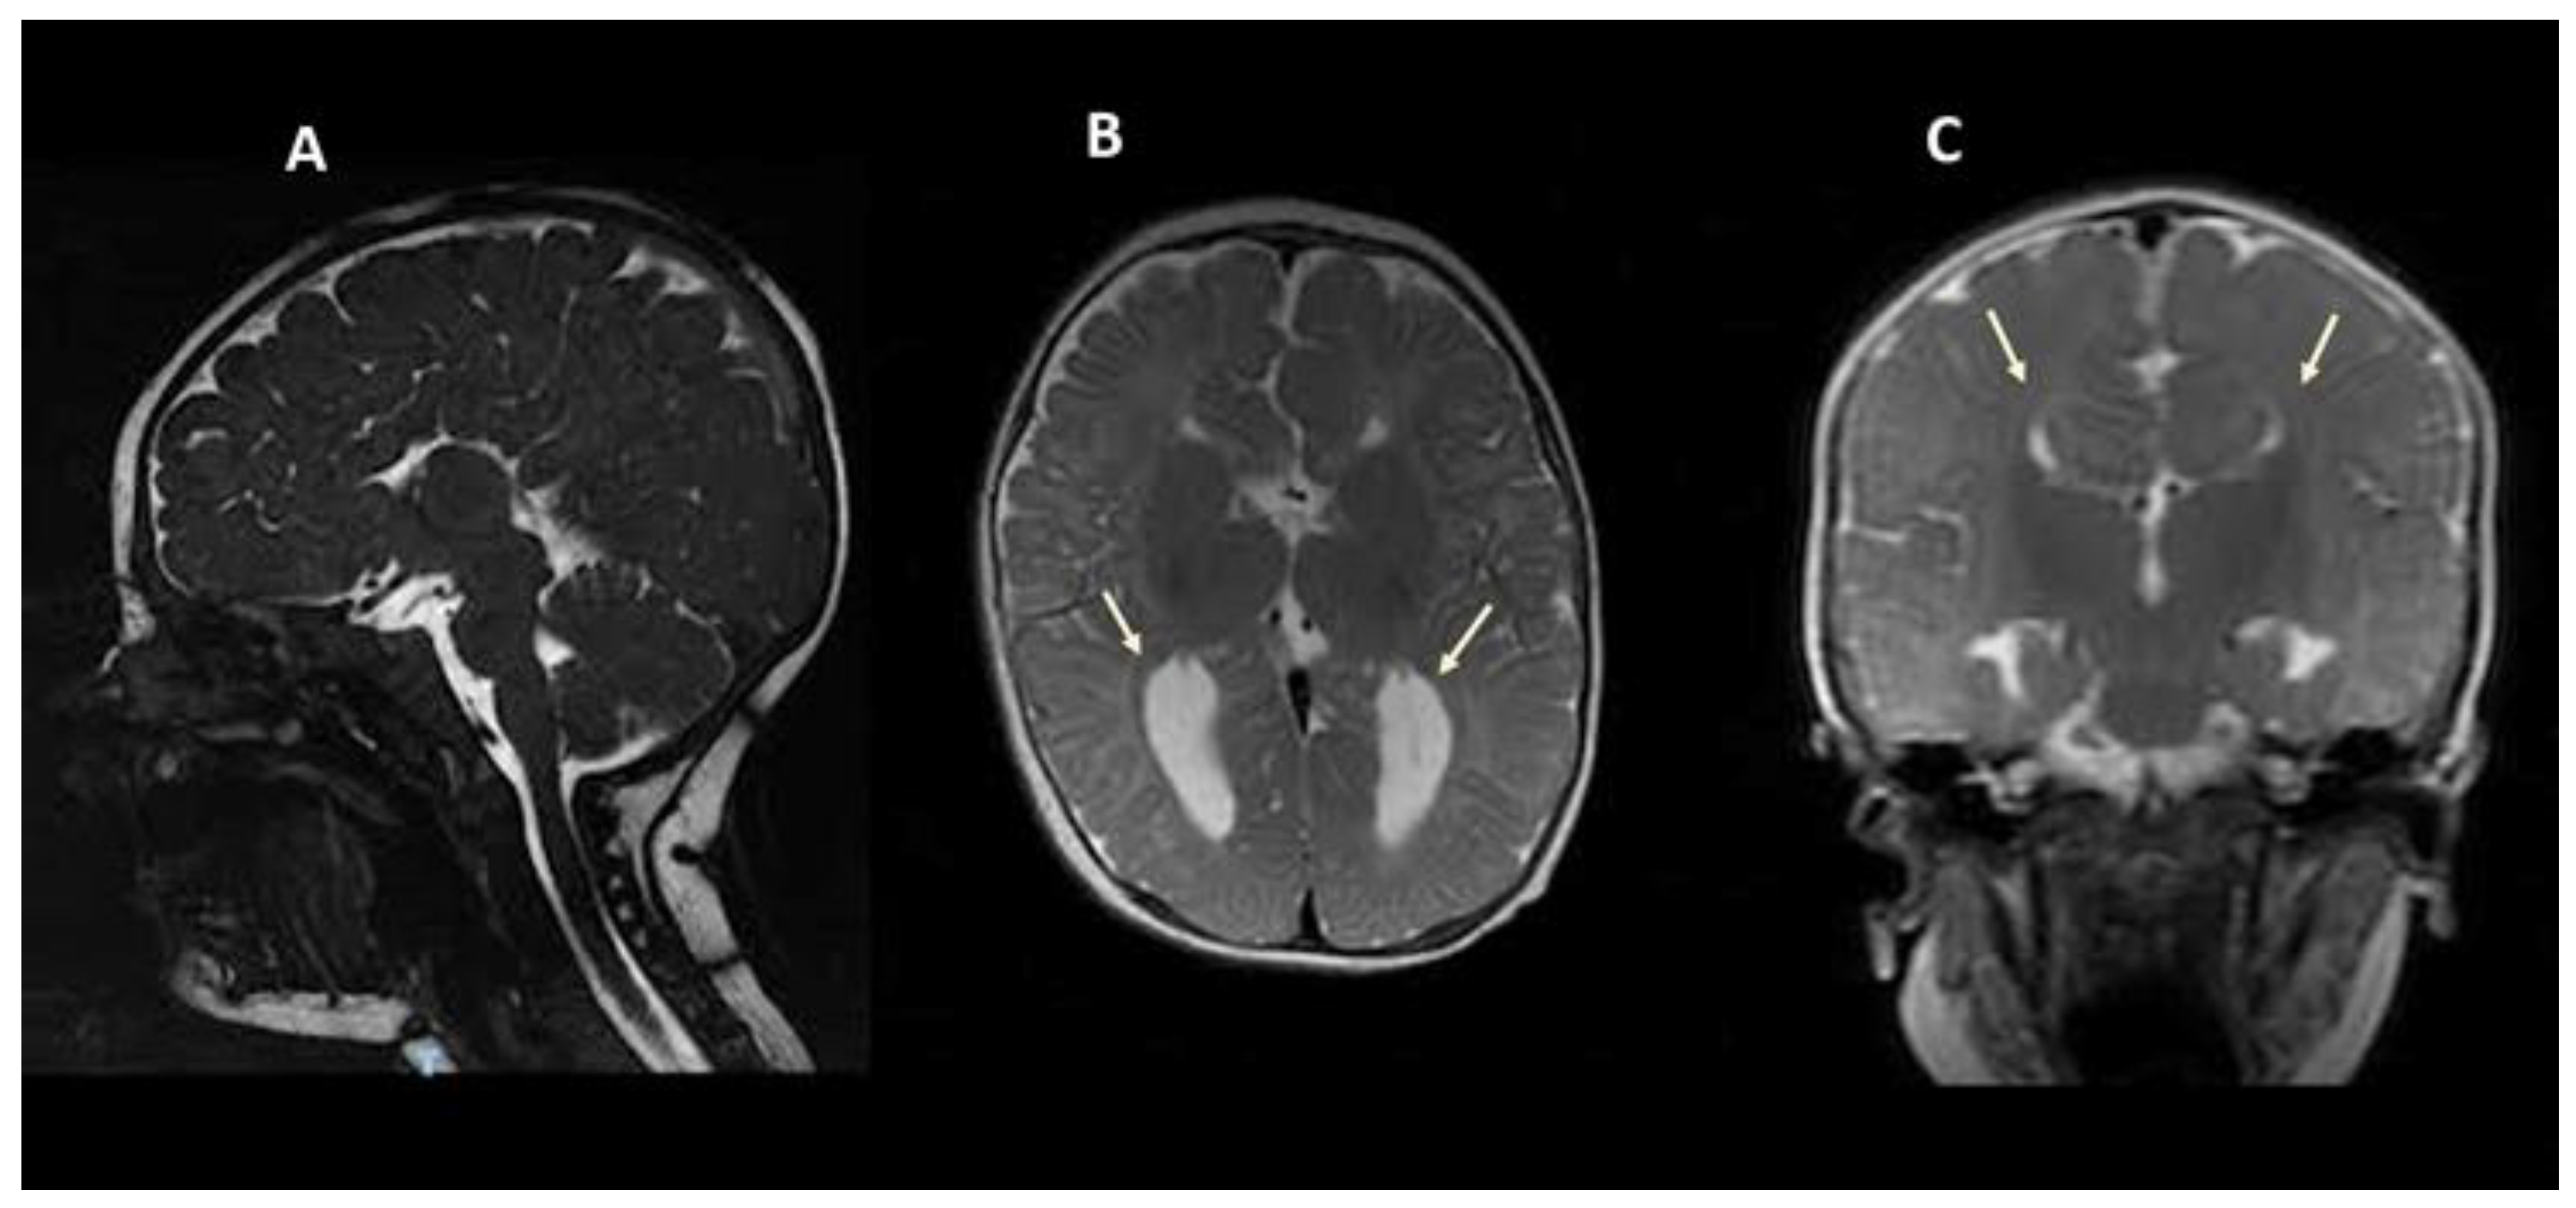

| M/7 | Caucasian | Global development delay | Low intellectual functioning | + | Alternating strabismus; language disorder; episodes of stiffness with hyperextension of the lower limbs | cACC | Colpocephaly | c.2426A>G/p.Tyr809Cys | This report |